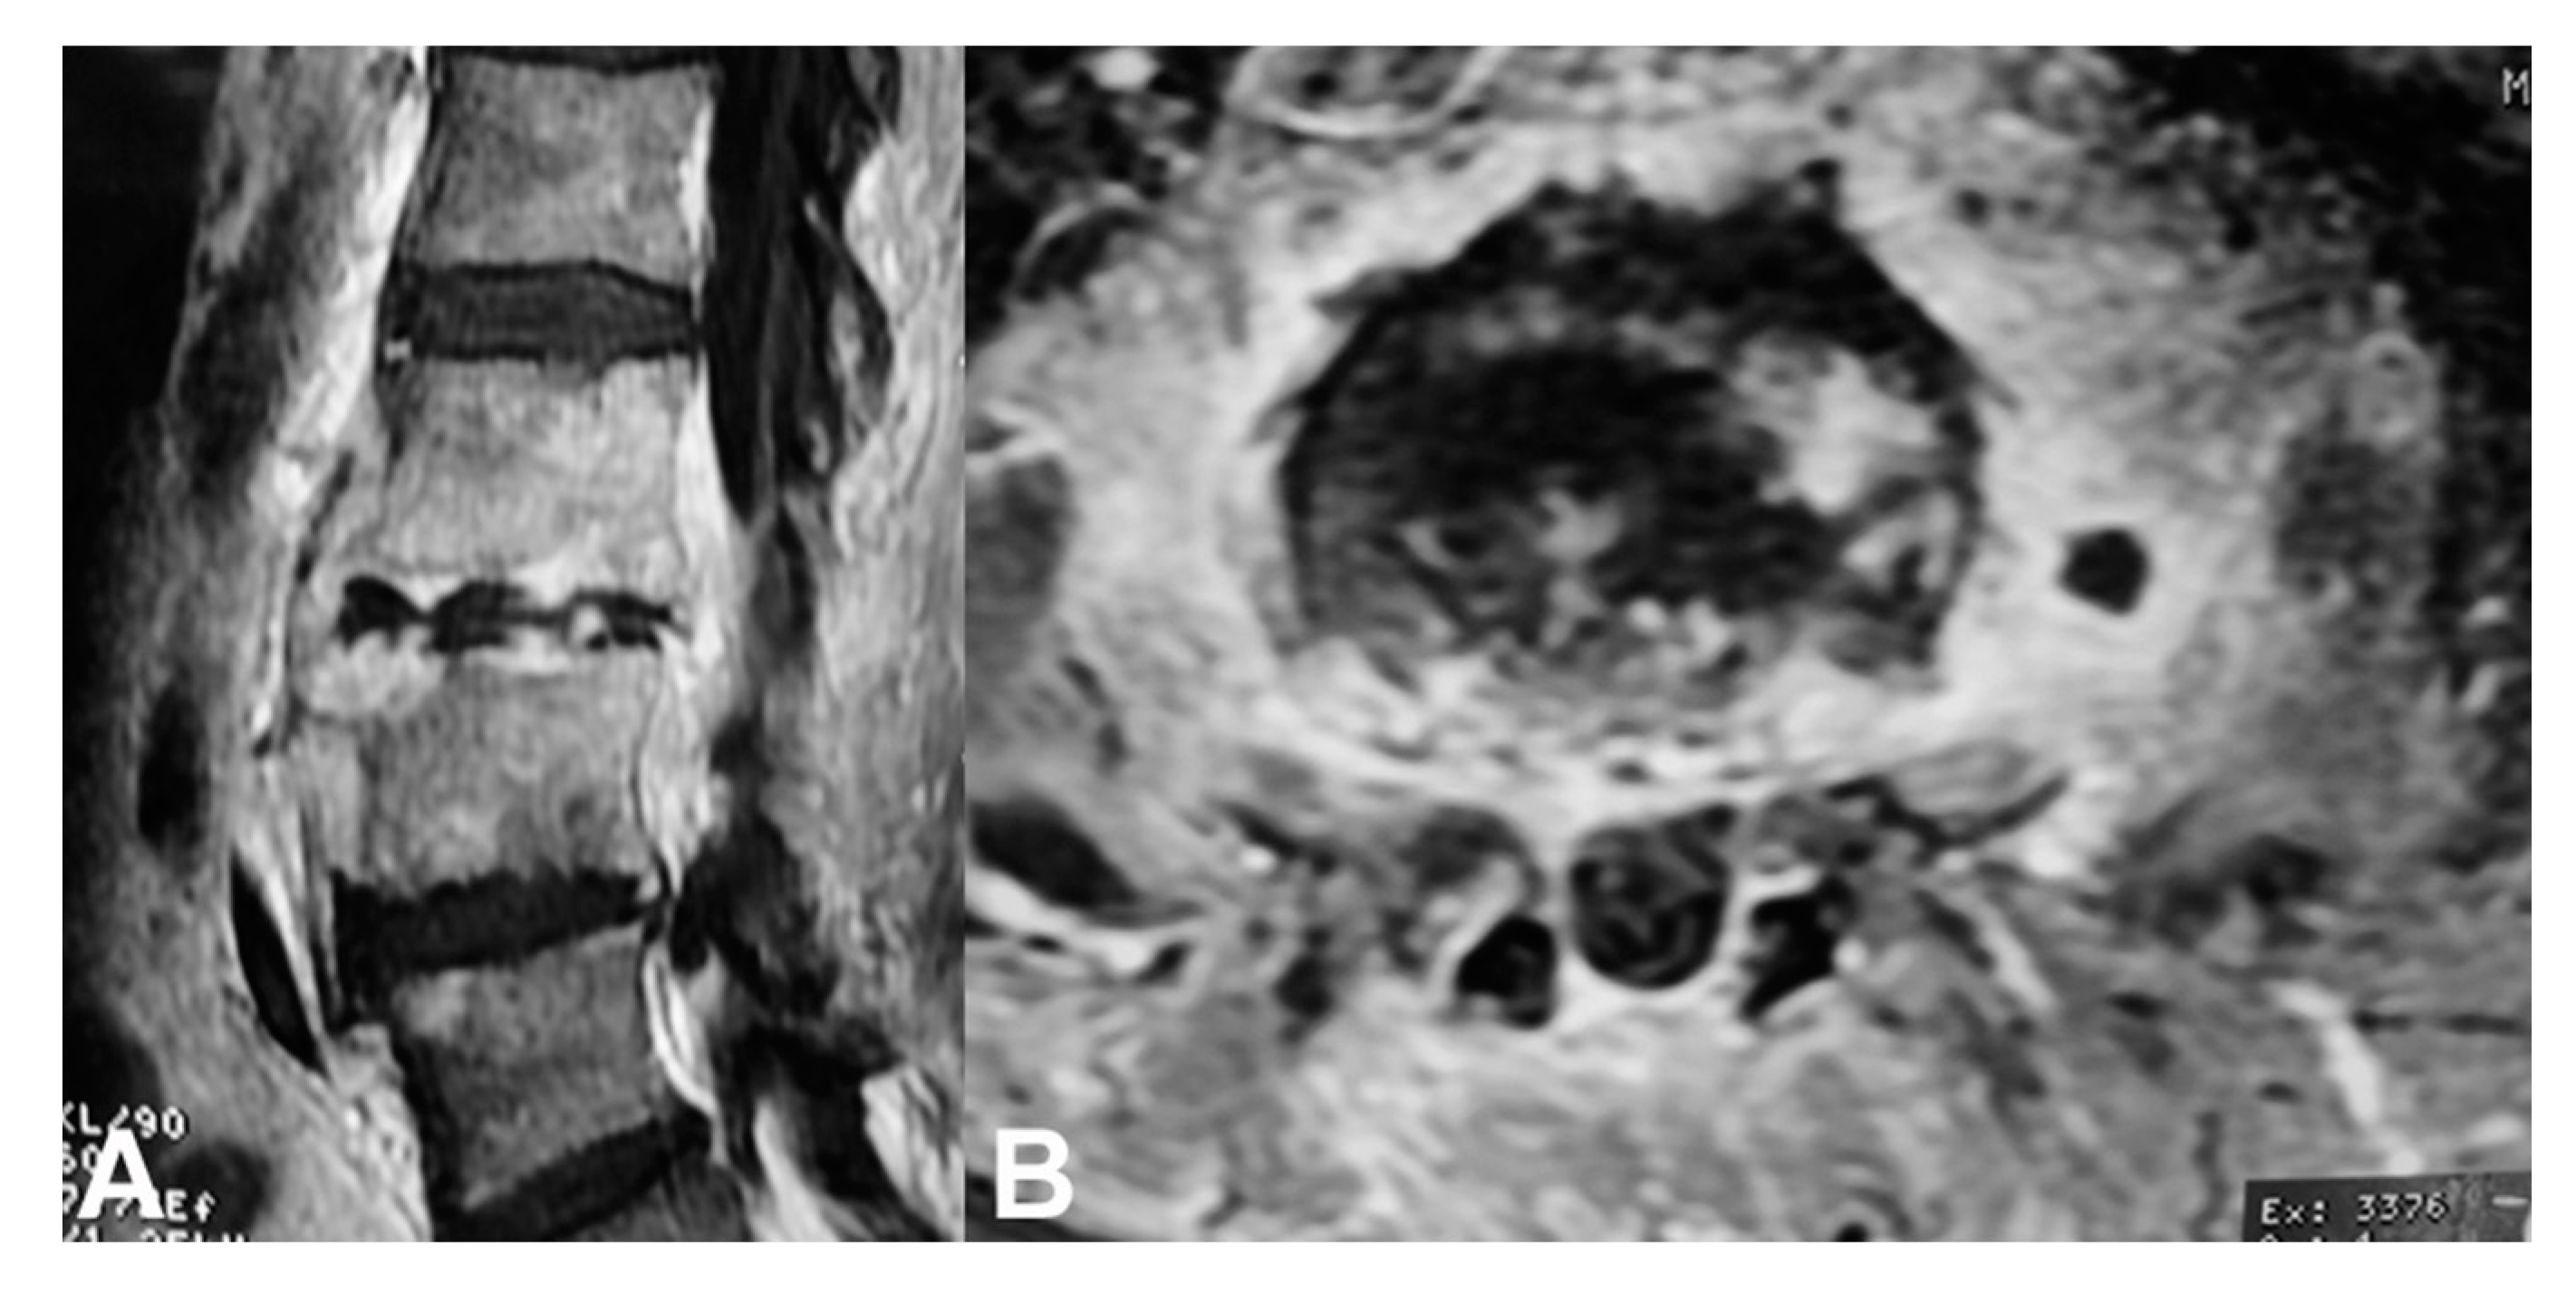

5. Diagnosis